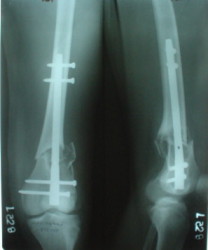

1

2

de> And perhaps you could show us also some of your results ,

de> that is (follow up) not immediate postop x rays.

I attached an example of C2 fracture with result of the same technique in 5 months.